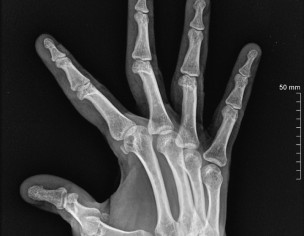

Not sure which treatment you are referring to. the Xrays show quite a bit of damage for someone who is just 40 yrs old. I suspect the patient may have inflammatory arthritis causing this. for this she should consult a qualified Rheumatologist for specialist treatment

I agree with Dr. Ashar, you are too young to have these x rays. See a rheumatologist soon.